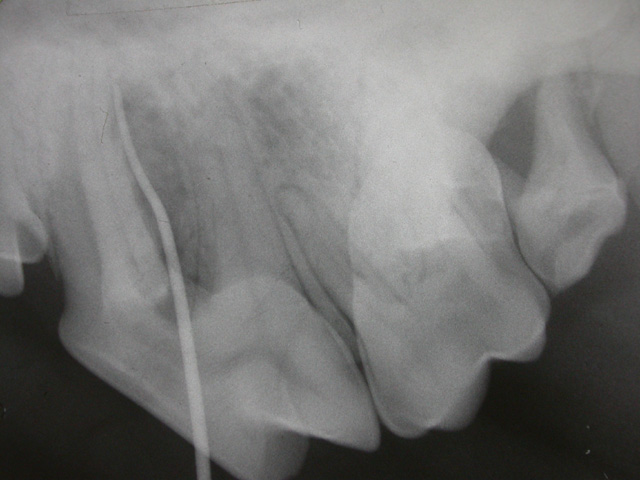

Oral Diagnoz ve Radyoloji